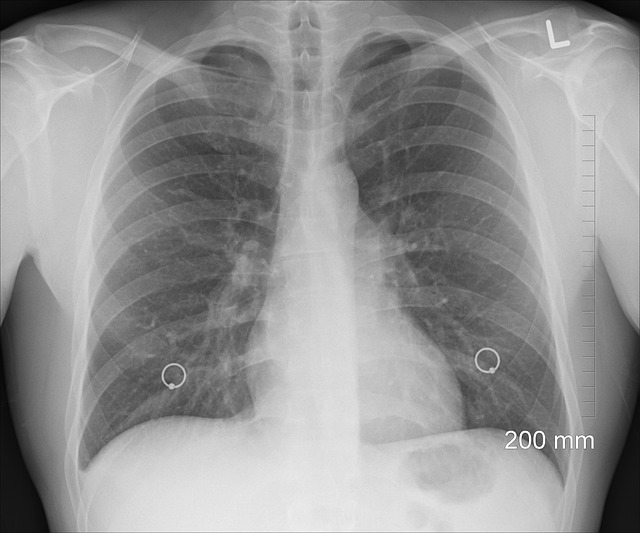

2) 폐암 진단방법

폐암 진단을 위해서 폐암초기 증상이 나타난다면 가벼운 증상이라도 병원을 찾아 진단을 받는 것이 중요합니다. 영상 검사와 생검 검사 두가지로 나뉘는데, 폐암의 위치와 크기에 따라서 파악하는데 사용되는 기본적인 X선검사, CT검사, PET검사 등이 있습니다. 폐조직을 직접 채취하여 병리학적으로 확인하는 방법으로, 폐암 진단에 따라서 가장 정확한 방법으로는 생검 검사를 추천드립니다.